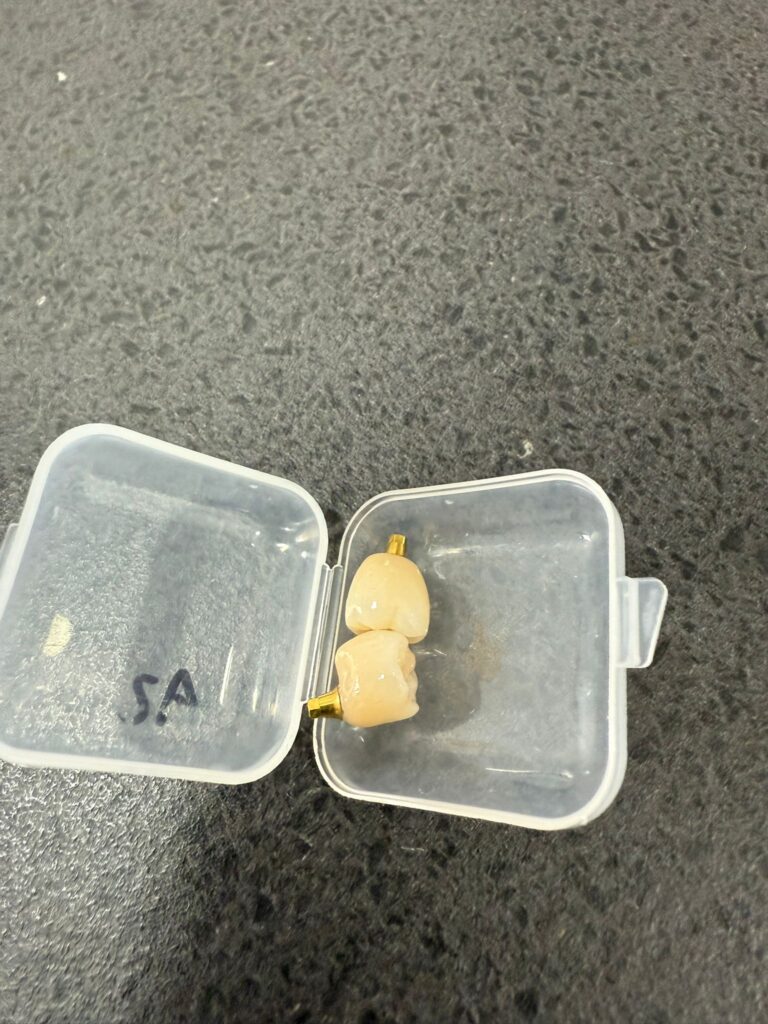

- Colocación de la corona personalizada: Una vez el implante es estable, diseñamos y colocamos la corona (el diente visible). Se fabrica a medida en color y forma para que encaje perfectamente con el resto de tus dientes.